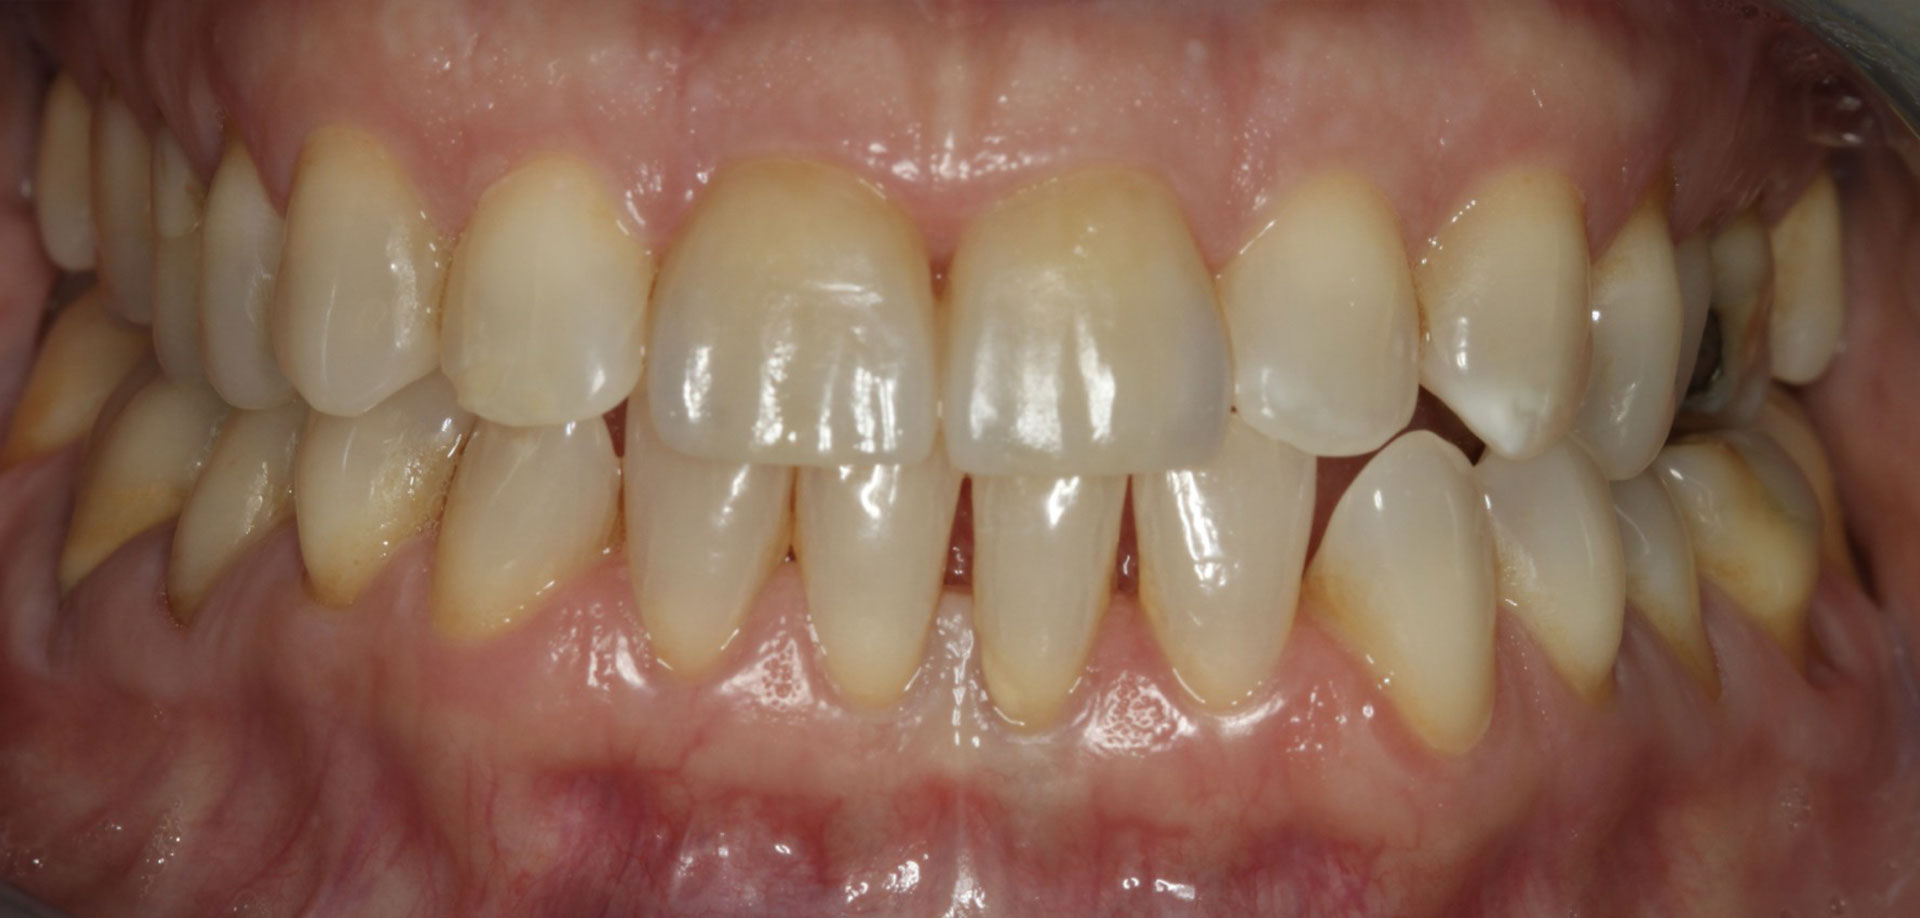

Presentamos una serie de casos clínicos, mostrando el antes y el después.

El paciente vino con una sonrisa con coloración más apagada y manchas. Tras el tratamiento con un blanqueamiento dental, se muestra una clara mejoría en luminosidad, con un aspecto homogéneo.